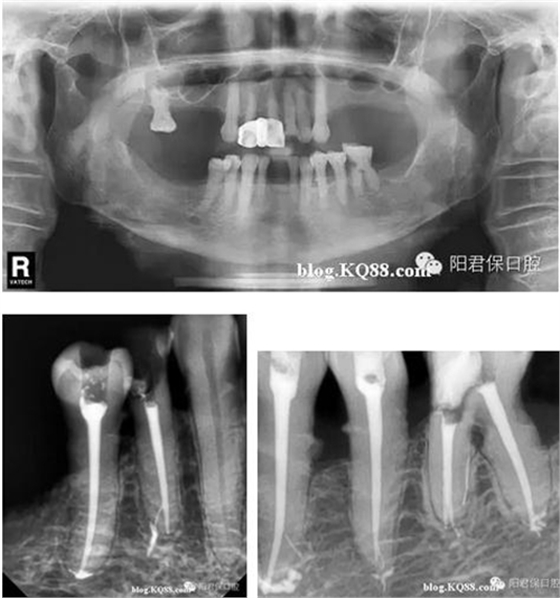

患者:姜XX 性別;女 年齡:65 根據(jù)齲壞程度、患者的癥狀、修復需要,且對收費及牙髓處理均征得同意后第一次行右下4、5,左下4、5、6;第二次行左下2,右下2 ,右上7一次性根管治療術(shù)。

術(shù)后見右下4,左下4均有側(cè)支充填,且位置對稱,左下6近中根中部有側(cè)支;左下5、左下6遠中根管均多個開口。

熱牙膠垂直加壓后有封閉劑和牙膠超填,但無術(shù)后反應。